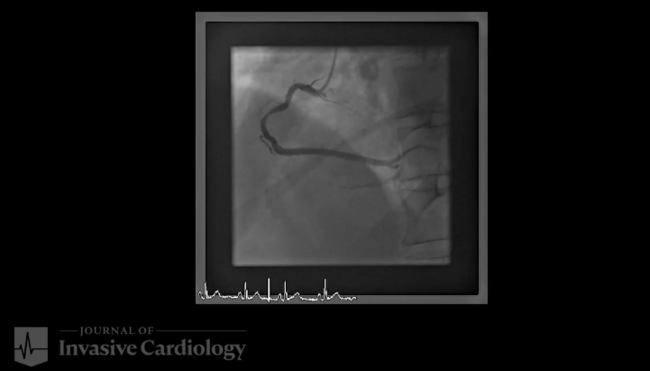

A 65-year-old man who presented with lateral ST-segment-elevation myocardial infarction was referred for primary percutaneous coronary intervention. J-wire and 5.2-Fr JR4 diagnostic catheter progression through right radial artery access was hampered by radial artery spasm and subclavian artery tortuosity. Then, a hydrophilic-coated guidewire was used to assist catheter advancement into the aortic root. Coronary angiography revealed an acute occlusion of the first obtuse marginal artery, which was successfully revascularized with 2 consecutive drug-eluting stents.